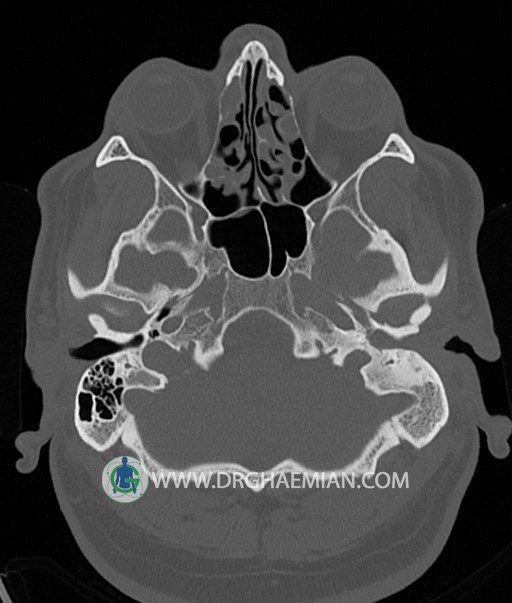

سی تی اسکن گوش داخلی به رادیولوژیست اجازه می دهد تا سطوح مختلف، یا اسلایس هایی از استخوان های که از جمجه به گوش می روند را از طریق امواج ایکس چرخشی مشاهده کند. در این کیس اودیت مدیا، ماستوئیدیت مزمن، اوتیت خارجی، انحراف سپتوم بینی، کونکا بولوزا و افزایش ضخامت سینوس ها مشاهده می شود.

در HRCT از استخوان تمپورال با مقاطع آگزيال ، ساژيتال و کرونال ظريف ( 0.6 mm ) :

– اپاسيتي گوش مياني چپ ناشي از وجود دانسيته نسج نرمي دراطراف استخوانچه ها همراه با اروژن اسکوتوم و

استخوانچه ها بدون جابجايي در رديف استخوانچه ها مشهود است که مطرح کننده اوتيت مديا همراه با نشانه

هاي مشکوک به کولستئاتوم مي باشد .

– اپاسيتي و اسکلروزيس ماستوئيد چپ نشانه ماستوئيديت مزمن

– اپاسيتي کانال گوش خارجي ناشي از دانسيتي نسج نرمي مطرح کننده external otitis